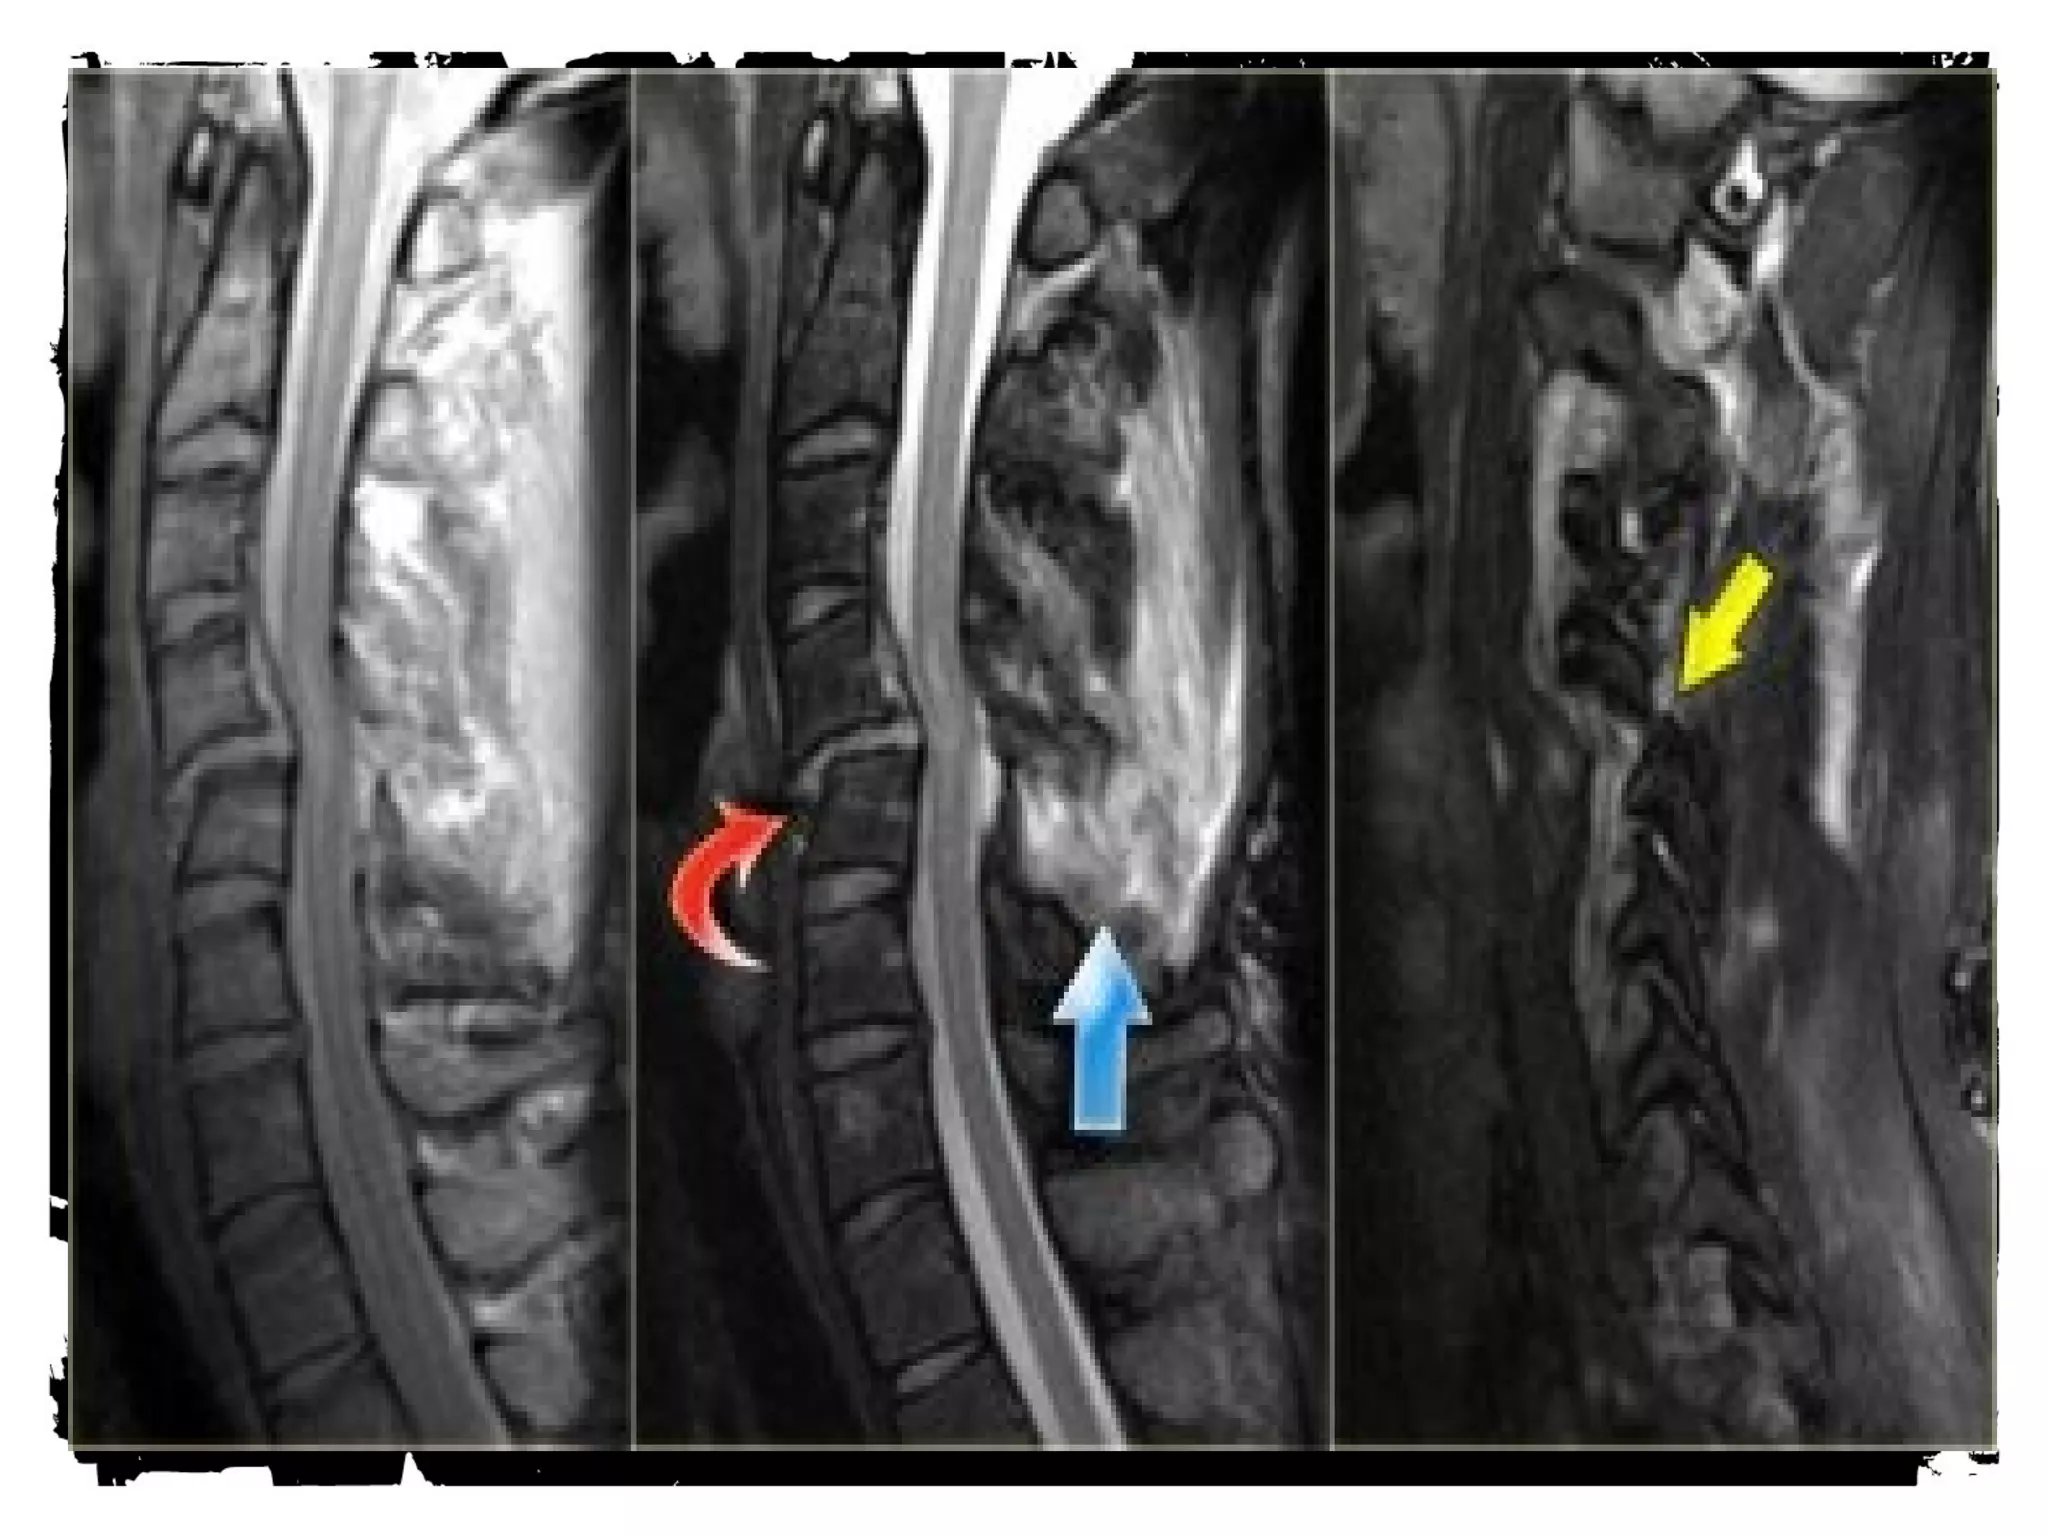

Spinal cord injury (SCI)

Spinal cord injury

There are two types of

injury to the spinal cord:

• Non-hemorrhagic with

only high signal on MR

due to edema.

• Hemorrhagic with areas of

low signal intensity within

the area of edema.

• There is a strong correlation

between the length of the

spinal cord edema and the

clinical outcome.

• The most important factor

however is whether there is

hemorrhage, since

hemorrhagic spinal cord

injury has an extremely poor

outcome.

Midsagittal (a) T1-weighted and (b) T2-weighted MR images obtained in 45-

year-old man with acute traumatic C5 through C6 mild SCI after a fall show

the distances of the spinal canal and spinal cord at the injury site (Di and di,

respectively), one segment below the injury site (Db and db, respectively), and

one segment above the injury site (Da and da, respectively) used to (a)

estimate the MCC and (b) measure spinal canal compression.

©2007 by Radiological Society of North America